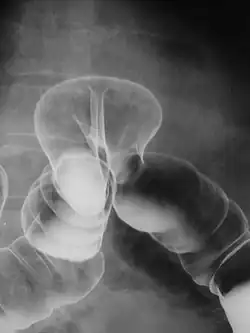

Контрастная рентгенография — группа методов рентгенологического исследования, основанных на контрастировании полых анатомических образований рентгеноконтрастными препаратами.

Контрастная рентгенография применяется для визуализации полых органов, когда необходимо оценить их локализацию и объём, структурные особенности их стенок, функциональные характеристики. При некоторых исследованиях (например, при ирригоскопии) также изучается структура стенок полых органов после их опорожнения от контрастного вещества.

Данные методы широко используются при рентгенологическом исследовании желудочно-кишечного тракта, органов мочевыделительной системы (урография), оценке локализации и распространённости свищевых ходов (фистулография) и т. д.